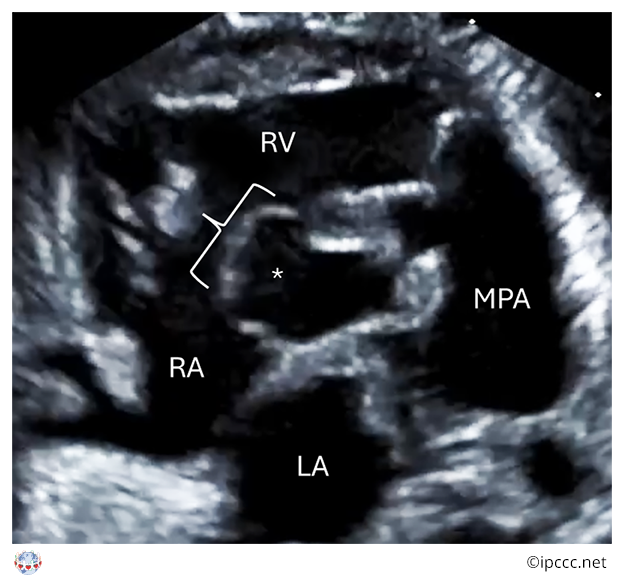

A congenital cardiac malformation in which there is a ventricular septal defect that usually, but not always, extends beneath the full annular length of the septal leaflet of the tricuspid valve and to the membranous septum, into the inlet component of the right ventricle in the absence of atrioventricular septal malalignment and of a common atrioventricular junction.

Echocardiogram